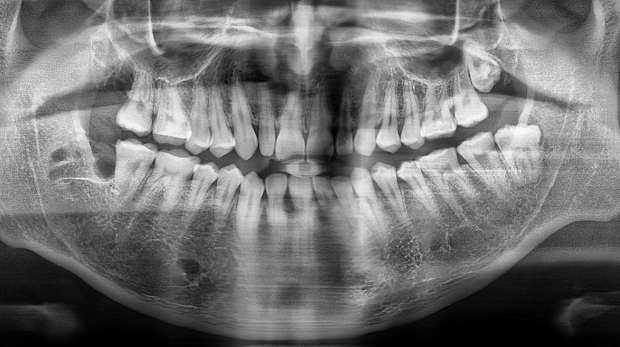

박** 환자분 (오른쪽 상하악 사랑니 동시 발치 케이스)

상악의 경우 단순매복으로 발치 및 동시에 하악 잇몸뼈에

깊게 박혀잇는 고난이도 케이스, 잇몸절개 후 치아 분리하여

발치하였으며